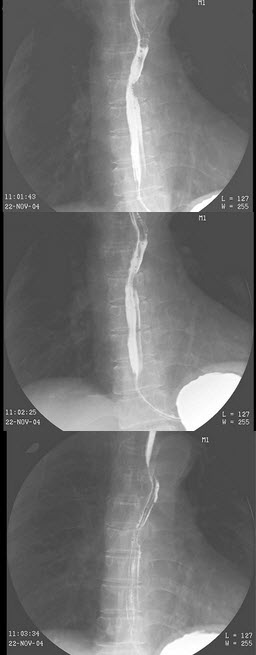

89、单项选择题

女,56岁,进行性吞咽困难2月,伴胸骨后针刺感入院,结合图像,最可能的诊断为()

A.正常表现

B.食管静脉曲张

C.食管上段癌

D.食管中段癌

E.食管下段癌